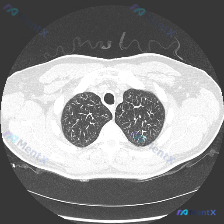

看到一个胸部CT肺尖层面的病例资料,整理了一下思路。这张图像是胸部CT肺尖层面的肺窗截图,先分析一下该层面的影像学表现: 初步影像学评估 该肺尖层面图像显示双侧肺尖部透亮度基本对称,肺实质未见明显局灶性密度增高或结构破坏。肺纹理走行自然,未见明显增粗、扭曲或聚集。气管位于正中,管腔通畅,形态规则。纵...